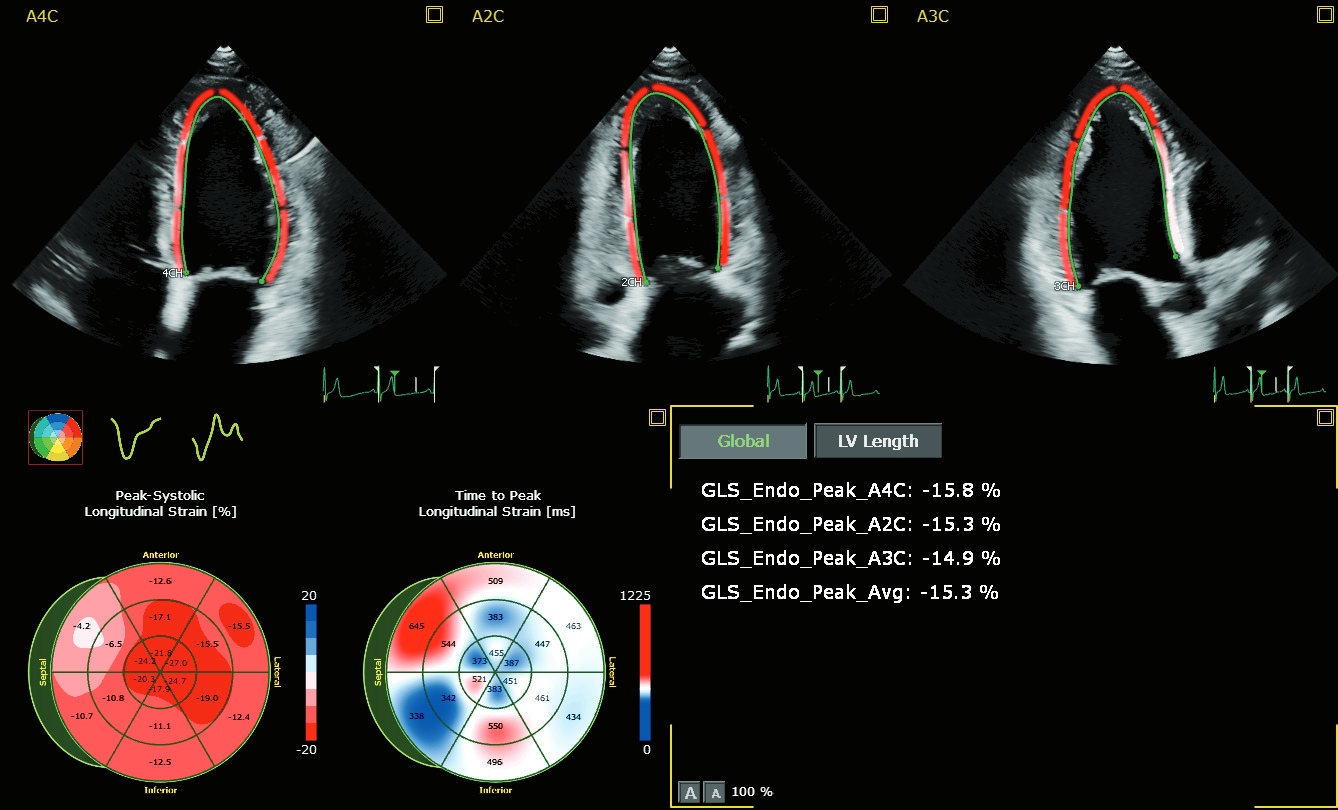

Dr. Teresa López-Fernández: Le CTRCD* est un phénomène continu qui commence par une lésion des cellules myocardiques et se poursuit par un dysfonctionnement progressif du ventricule gauche qui, s'il n'est pas pris en compte et traité, conduit progressivement à une IC manifeste13. La 2D identifie trop tard la cardiotoxicité, uniquement lorsqu'une altération fonctionnelle importante est déjà survenue, ce qui exclut toute chance de prévention efficace, car plus le temps passe, plus les possibilités de guérison se réduisent.14 La 3D augmente la capacité à détecter des changements plus faibles de la FEVG par rapport à la 2D et offre une variabilité temporelle plus faible que la 2D pour le suivi longitudinal des patients subissant une chimiothérapie. La technique se compare bien à la CMR et les valeurs de FE sont identifiées par la 3D plus tôt que par la 2D chez les patients cancéreux qui développent une cardiotoxicité 3,4,15. Malgré ces avantages, le temps et l'expertise nécessaires pour analyser l'écho 3D se sont avérés être un obstacle à l'acceptation clinique à grande échelle. Pour améliorer l'intégration de la 3D dans la pratique clinique, nous avons besoin d'un logiciel de quantification entièrement automatisé, comme le Dynamic HeartModel A.I, pour à la fois réduire la courbe d'apprentissage et minimiser la consommation de temps. Une autre question importante est de savoir si la surveillance cardiaque basée uniquement sur la FE est suffisante. Comme vous le savez, le cœur a une structure hélicoïdale composée de trois couches coordonnées de fibres myocardiques et la FEVG n'évalue que la fonction radiale. La composante longitudinale de la déformation du VG est plus sensible que la 2D pour détecter la présence de maladies myocardiques précliniques dans différents scénarios cliniques, en particulier dans la population générale à risque de IC26 . Il a été démontré que la déformation longitudinale globale est une technique réalisable sans nécessiter de temps supplémentaire pour l'acquisition d'images et avec une analyse minimale en utilisant de nouvelles méthodes automatiques. La GLS a une meilleure reproductibilité que la 2D standard lorsqu'elle est réalisée par des opérateurs formés ou après une courte période de formation. En attendant les résultats de l'essai Succour,17 une stratégie de surveillance basée sur la 3D et la GLS pour identifier les changements précoces de la fonction ventriculaire et guider la thérapie cardioprotectrice semble être la meilleure stratégie chez les patients à haut risque subissant une chimiothérapie cardiotoxique.

Dr. Teresa López-Fernández: Les patients recevant des traitements anticancéreux doivent être considérés comme présentant un risque d'insuffisance cardiaque (insuffisance cardiaque de stade A) et la surveillance de la fonction ventriculaire gauche est recommandée pour l'identification précoce des lésions myocardiques asymptomatiques (insuffisance cardiaque de stade B)18. Avant d'administrer des traitements potentiellement cardiotoxiques, il est recommandé de procéder à un dépistage complet, y compris une évaluation par écho, afin d'exclure les problèmes cardiaques pertinents et d'optimiser la thérapie CV si nécessaire. L'écho de base est particulièrement importante pour évaluer le risque de cardiotoxicité chez les patients présentant des problèmes CV préexistants ou ayant déjà subi des traitements anticancéreux. Nous savons qu'une FEVG de base réduite ou faiblement normale (50-55%) triple presque le risque d'événements cardiaques29. Chez ces patients, dont la FEVG normale est faible, ou chez ceux qui présentent un risque cardiovasculaire plus élevé, la FEVG de base améliore encore la prédiction de l'IC20. Pendant la phase active du traitement, l'échocardiographie joue un rôle essentiel tant du point de vue du diagnostic que du pronostic. La stratégie de surveillance de l'écho dépend du schéma thérapeutique prévu et des risques encourus par les patients. La fonction ventriculaire gauche est généralement réévaluée tous les 3 à 6 mois, en cas de suspicion d'insuffisance cardiaque et à la fin du traitement1,2,21. Le dépistage en série permet une identification et une prise en charge précoces des CTRCD*. La stratégie idéale consiste à comparer les mesures 3D et GLS obtenues pendant la chimiothérapie avec celles obtenues au départ, ce qui permet au patient de servir de contrôle. Le plus fort prédicteur de CTRCD*, défini comme un dysfonctionnement subclinique du ventricule gauche, est une baisse relative de la GLS > 15 % par rapport au niveau de base1,3,14. Si les mérites de l'échocardiographie dans la détection des CTRCD* chez les patients atteints de cancer sont reconnus, il reste de réels défis à relever dans le cadre cardio-oncologique - tels que la qualité de l'image, la précision, les coûts, la disponibilité et la nécessité de former des spécialistes pour aider à la prise de décision clinique.